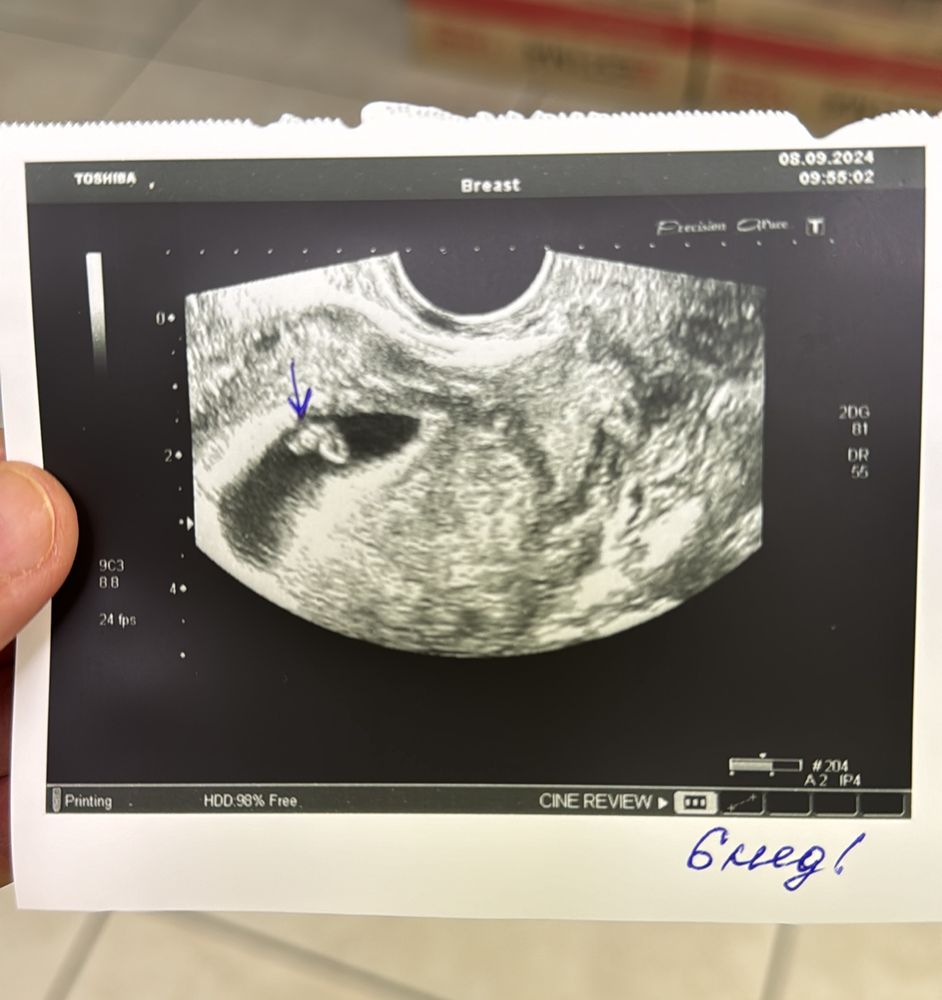

Здравствуйте. Мне тоже посмотрите пожалуйста кто разбирается? срок 6 нед 5 дн, узи через животик - т.е. абдоминальное. Спасибо.

Если узи трансвагинально делали, то я напророчу вам мальчика. Сама этим методом заинтересовалась в Б, изучала его, интересно было. У меня совпало. Метод имеет погрешность 3%, но плюс к тому его ещё часто неверно трактуют- сроки не соблюдают (до 8 недель, позже неинформативно), путают метод узи (по животу или вагинально). По моим данным если узи до 8 недель выполнено трансвагинальным датчиком, то прикрепление слева - мальчик, справа - девочка. Абдоминально - наоборот. А желаю вам девчуху для разнообразия 😃

Посмотрите пожалуйста, видно здесь, с какой стороны? А то я так и не поняла)))

Если трансвагинально, то, вроде, девочка. Но вот, у автора, смотрю, я ошиблась 😁